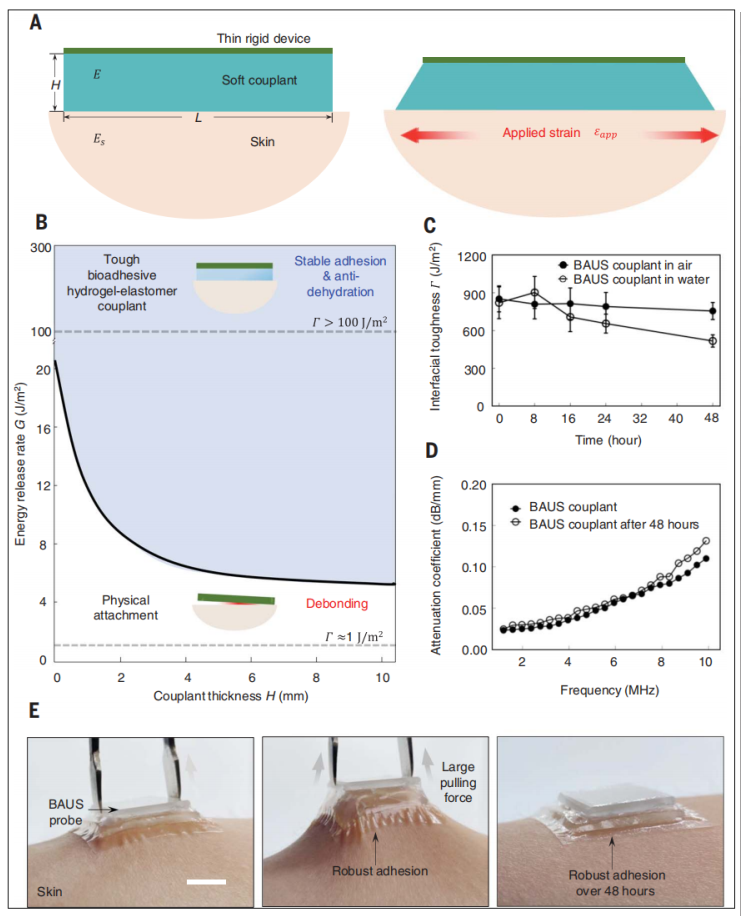

为了定量地验证BAUS装置在动态身体运动的情况下能够牢固地附着在皮肤上,本文开发了一种刚性体装置模型,通过柔软的耦合剂层附着在皮肤上(图2A)。

当皮肤被施加应变拉伸时,耦合-皮肤界面边缘会产生裂纹并扩展。裂纹扩展由能量释放率G(单位面积内,裂纹扩展时耦合皮肤系统中释放的弹性势能)驱动,由界面韧性Г(裂纹单位面积扩展所需的能量)抵抗。在图2B中,我们计算耦合皮肤系统在平面应变条件下的能量释放率G,器件长度L为2cm,皮肤的典型应变为20%。为简化计算,皮肤和耦合层均为杨氏模量均为100 kPa的不可压缩线性弹性材料。当能量释放速率高于界面韧性,即G >Г时(图2B中未遮挡区域),裂纹在界面上扩展,器件脱离皮肤。当刚性器件在没有耦合剂(耦合剂厚度H = 0)的情况下附着在皮肤上时,其韧性约为1J/m2,刚性器件会从皮肤上脱落。相比之下,当刚性器件通过BAUS耦合剂粘接在皮肤上时,无论是在空气中还是在水下,其界面韧性都超过500 J/m2(图2C),此时无论偶联剂厚度如何,器件都能牢固地粘接在皮肤上。

为了评价BAUS耦合剂在猪皮上的粘附性能,我们进行了标准的90°剥离试验(ASTM D2861),以测量弹性体膜通过生物粘附层粘附在猪皮上的界面韧性(有关测试的细节,请参阅材料和方法)。由于猪皮与人的皮肤相似,我们选择猪皮作为评估粘附性能的模型组织。弹性体膜可牢固地粘附在猪皮上,界面韧性为853J/m2。当粘附样放置于空气中(相对湿度30~50%;24°C),48 h后界面韧性降至756J/m2;当试样置于水中模拟潮湿环境时,48小时后界面韧性降至518 J/m2。这些结果(图2,C和E)表明,在干燥和潮湿的环境中,生物黏附层能够将BAUS装置牢固地粘附在皮肤上超过48小时。通过BAUS偶联剂的一端进行剥离,可以将BAUS器件与皮肤分离的同时不留下任何残留(见图S12)。相比之下,典型液体和固体水凝胶耦合剂和弹性体耦合剂(包括硅胶、聚氨酯和水烯)界面韧性都小于10 J/m2,从而超声探头不能在皮肤上稳定粘附。虽然3M VHB丙烯酸胶带在空气中48小时以上仍能保持较高的界面韧性(大于456J/m2),但是在水中界面韧性下降至27 J/m2,在潮湿环境中将可能导致粘接失败。

除此之外,研究团队还分别对BAUS装置的佩戴舒适度、耦合剂的声学性能、探头信号性能、成像分辨率、稳定性、热学性能分别进行了定量实验。限于篇幅原因不详细展开,感兴趣的读者可以自行阅读原文。

选段总结:能量释放率G与界面韧性Г的相对大小关系决定了BAUS装置能否牢靠的黏附在皮肤上。前者(能量释放率G)驱动裂纹扩展,后者(界面韧性Г)抵抗裂纹扩展,BAUS装置的界面韧性Г会随着时间、环境温湿度的变换而变化,当G>Г时装置会逐渐脱落。最终经实验测定,在48h间隔,空气相对湿度30~50%,24°C的情况下,BAUS始终保持高的界面韧性Г(高于3M VHB丙烯酸胶带),除此之外,研究人员还详细测定了BAUS装置的声学性能、探头信号性能、成像分辨率、稳定性、热学性能。

图2. BAUS器件的附着力和声学性能